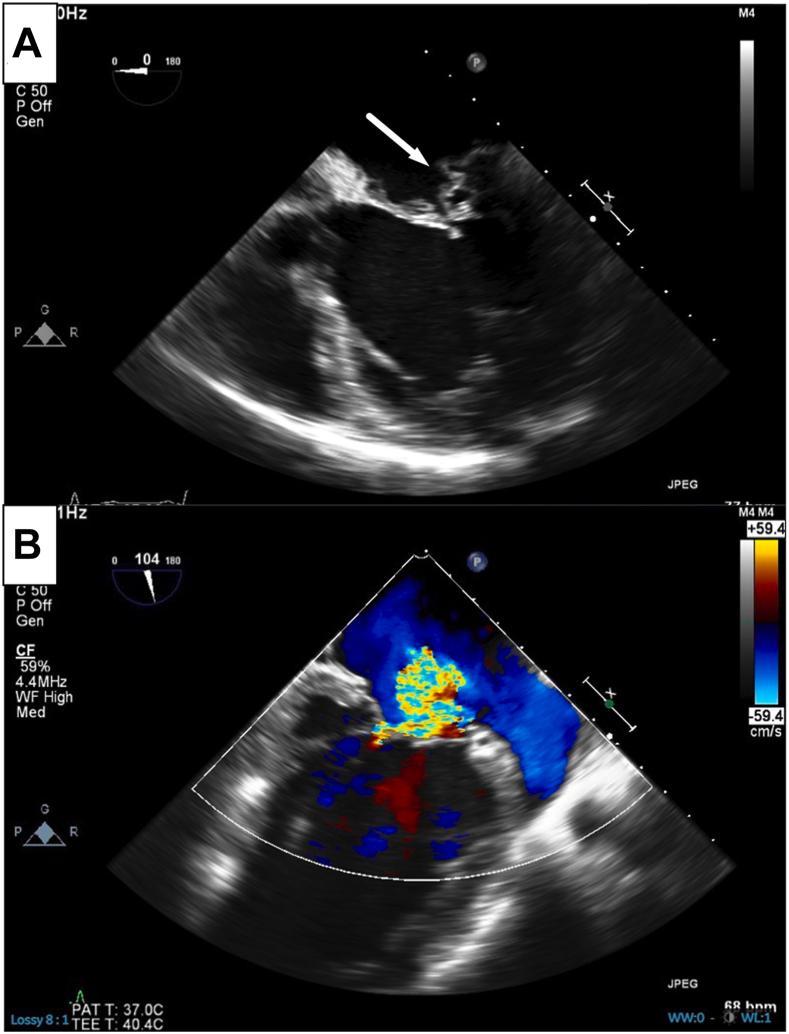

A 53-year-old male individual with chronic severe mitral regurgitation presented with biventricular dysfunction, pulmonary hypertension, and atrial fibrillation. Echocardiography demonstrated a posterior leaflet prolapse with malcoaptation. Mitral valve repair and Maze procedure were performed, revealing absent chordae and direct connection from the anterolateral papillary muscle to the posterior leaflet, consistent with partial mitral arcade. Post bypass, left ventricular dysfunction was addressed by intraaortic balloon pump placement and delayed sternal closure. Post chest closure echocardiography showed no residual mitral regurgitation and restored biventricular function. This case highlights a rare presentation of mitral regurgitation with unique anatomical anomaly, successfully managed with a comprehensive surgical approach.

摘要

一名53岁患有慢性重度二尖瓣反流的男性患者出现双心室功能障碍、肺动脉高压和心房颤动。超声心动图显示后叶脱垂伴对合不良。进行了二尖瓣修复和迷宫手术,发现腱索缺失,前外侧乳头肌与后叶直接相连,符合部分二尖瓣弓的表现。体外循环后,通过置入主动脉内球囊泵和延迟胸骨闭合来处理左心室功能障碍。胸骨闭合后超声心动图显示无残余二尖瓣反流,双心室功能恢复。该病例突出了二尖瓣反流伴有独特解剖异常的罕见表现,通过综合手术方法成功治疗。